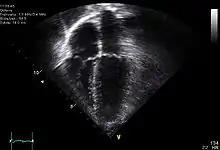

Diagnosis of traumatic cardiac arrest is initially made with electrocardiogram with EMS or in the emergency department. Clinicians will also order diagnostic testing that may include chest x-ray, bedside ultrasound and echocardiogram, and blood gas levels. A type and cross will be ordered to match the patient to receive blood transfusion if necessary.